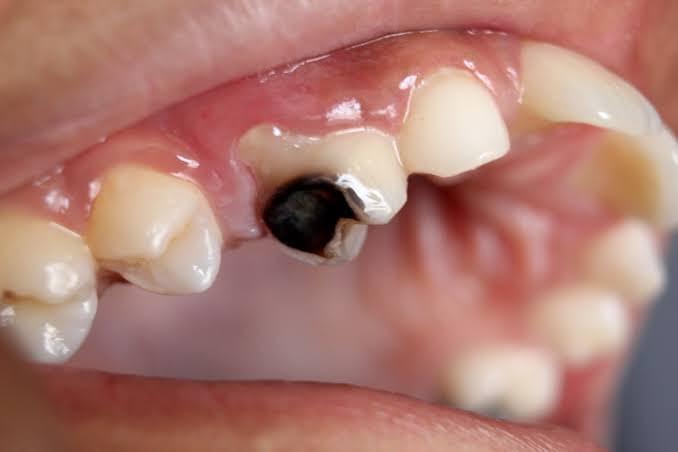

- Tooth Decay - Tooth Decay (dental caries), is a loss of tooth structure caused by bacteria breaking down sugars and the subsequent release of acids. If tooth decay is left untreated, it can cause severe pain and swelling, resulting in tooth loss.  - Tooth Decay happens as a result of several factors, including bacteria (plaque), sugar intake frequency and time*. - Bacteria - microorganisms that can digest sugars from your diet - Sugar - source of energy that bacteria needs to grow and cause decay - Time - tooth decay is a long-term process and doesn't happen overnight - *If you remove one or more of these factors, tooth decay may be preventable and even stop progressing entirely.  - There are many patterns of tooth decay, and the exact size/depth can be unpredictable.